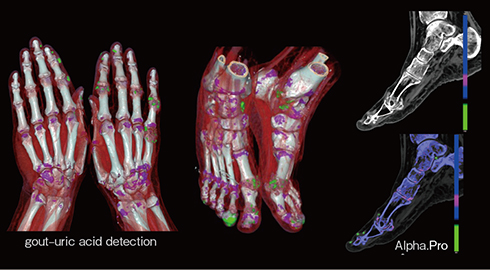

PCD-CTの超高解像度とSpectralデータ再構成によって,骨折や骨組織の浮腫,半月板や軟骨,関節内出血などを明瞭に描出でき,詳細な評価が可能である。

また,代謝性疾患の描出も可能である。痛風の症例(図7)では,手足の関節に尿酸沈着や痛風結節が多数描出されている。dual energy CTと同様の解析結果を,より高解像度に得ることができる。

図7 Spectral解析による痛風の尿酸沈着および痛風結節の描出